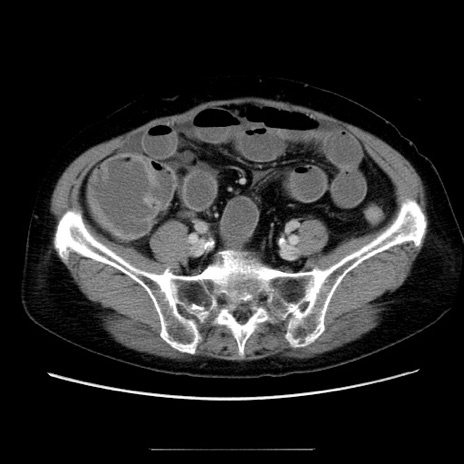

症例5(横断像)

【症例】70歳代女性

【主訴】お腹が張る

【現病歴】1週間くらい前から腹部膨満の自覚あり。昨日夜から増悪したため、本日救急外来受診。

【身体所見】意識清明、BT 36.5℃、BP 165/106mmHg、HR 80bpm、SpO2 98%、腹部:膨満、軟、自発痛・圧痛なし、触診にて不快感あり、腸蠕動音:減弱

【データ】WBC 12600、CRP 1.04